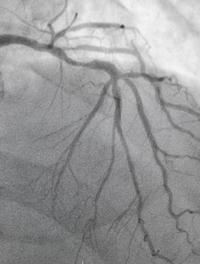

FA de novo : ablation ou antiarythmiques en première intention ?

En présence d’une FA récente, les preuves de la sécurité et de l’efficacité de l’ablation en première intention, comparée au traitement antiarythmique, demeurent controversées. Une revue systématique avec méta-analyse apporte une réponse.